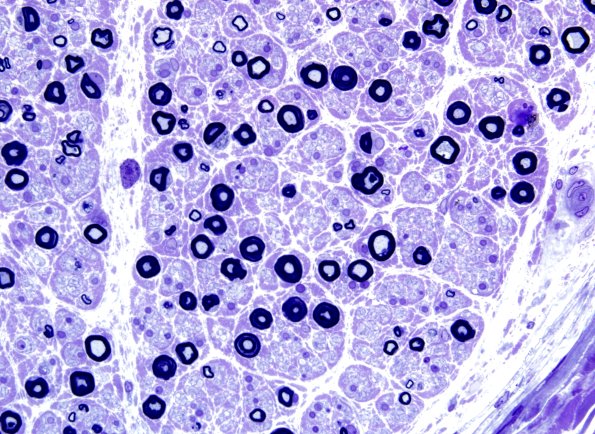

Washington University Experience | PERIPHERAL NEUROPATHY | 4 AXONAL DEGENERATION | 2 Plastic Sections | 21A3 Small MF loss (Case 21) Plastic 3.jpg

Small myelinated axons are more substantively lost; in addition, the number of small fibers may be artificially enhanced as part of regeneration of large degenerated axons which, if subtracted, would further enhance the loss of small myelinated axons. Regenerative clusters are identified. Multiple axons are thin for axon caliber, evidence for axonal regeneration.